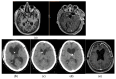

Low- or very-low-pressure hydrocephalus is a serious and rare phenomenon, which is becoming better known since it was first described in 1994 by Pang and Altschuler. Forced drainage at negative pressures can, in most cases, restore the ventricles to their original size, thus achieving neurological recovery. We present six new cases that suffered this syndrome from 2015 to 2020: two of them after medulloblastoma surgery; a third one as a consequence of a severe head trauma that required bifrontal craniectomy; another one after craniopharyngioma surgery; a fifth one with leptomeningeal glioneuronal tumor; and, finally, a patient carrier a shunt for normotensive hydrocephalus diagnosed ten years before. At the moment of development of this condition, four of them had mid-low-pressure cerebrospinal fluid (CSF) shunts. Four patients required cerebrospinal fluid (CSF) drainage at negative pressures oscillating from zero to -15 mmHg by external ventricular drainage until ventricular size normalized, followed by the placement of a new definitive low-pressure shunt, one of them to the right atrium. The duration of drainage in negative pressures through external ventricular drainage (EVD) ranged from 10 to 40 days with concomitant intracranial pressure monitoring at the neurointensive care unit. Approximately 200 cases of this syndrome have been described in the literature. The causes are varied and superimposable to those of high-pressure hydrocephalus. Neurological impairment is due to ventricular size and not to pressure values. Subzero drainage is still the most commonly used method, but other treatments have been described, such as neck wrapping, ventriculostomy of the third ventricle, and lumbar blood patches when associated with lumbar puncture. Its pathophysiology is not clear, although it seems to involve changes in the permeability and viscoelasticity of the brain parenchyma together with an imbalance in CSF circulation in the craniospinal subarachnoid space.